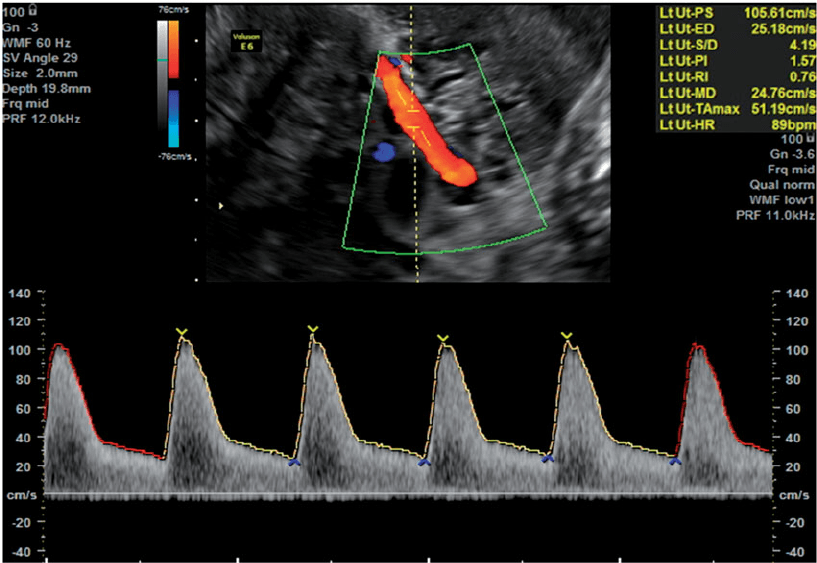

• Uterine Artery Doppler

• Uterine Artery Doppler measurement.